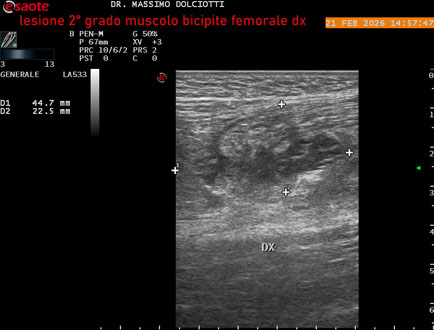

Ecografia del: 21/02/2026

Età Paziente: M 49 anni

Motivazione dell'esame: da 10 giorni dolore insorto durante la corsa.

Commento all'esame: le immagini ed il video documentano, al muscolo bicipite femorale destro, in sede prossimale, area disomogenea, ipoecogena, delle dimensioni di 27 x 24 mm (misura ottenuta per asse corto o trasversale) e delle dimensioni di 51 x 33 mm (misura ottenuta per asse lungo o longitudinale), da ricondurre a lesione muscolare di 2° grado con modica raccolta sieroematica intramuscolare.

Conclusioni: lesione di 2° grado al muscolo bicipite femorale destro (grade 2 injury to the right biceps femoris muscle).